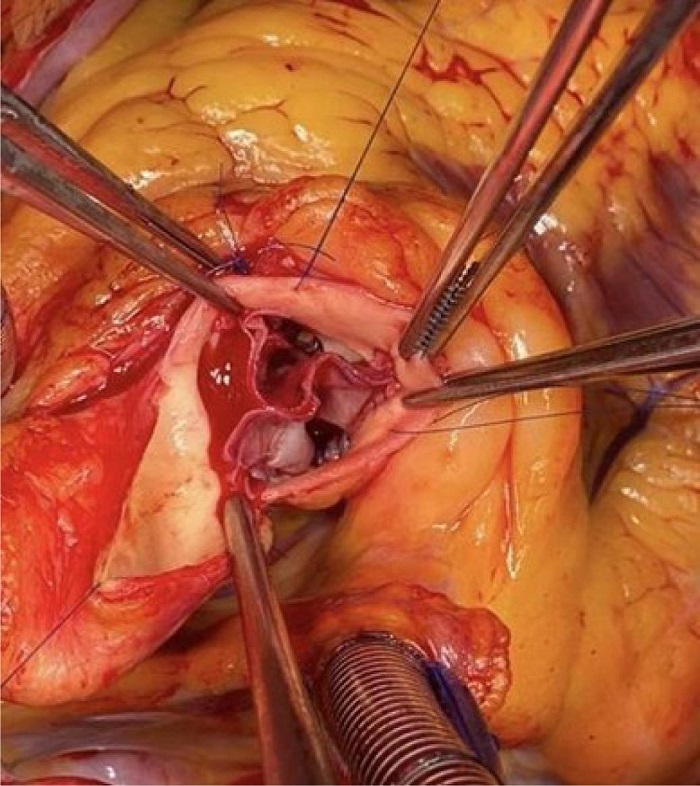

Each cusp is sutured to the native annulus using continuous polypropylene suture. The commissures are fixed with separate polypropylene sutures reinforced with Teflon™ pledgets that remain on the outside of the aortic wall (Figure 2).

A transesophageal echocardiogram is performed after coming off CPB to assess valve morphology, valve area, coaptation surface of the cusps, absence of insufficiency, and transvalvular gradient (Figure 3).